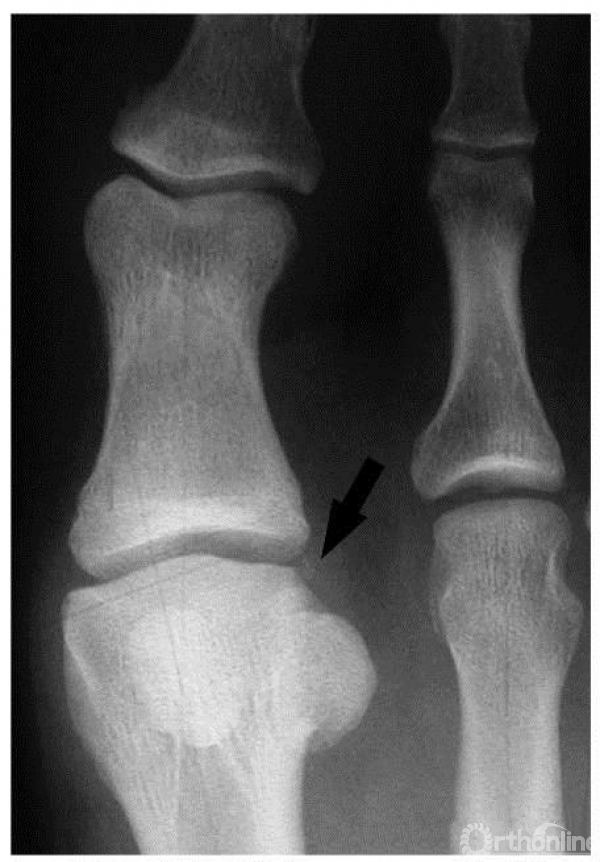

1期:正位x线上,箭头示外侧小的骨赘形成,关节间隙完好

1期:侧位x线上,箭头示小的背侧骨赘